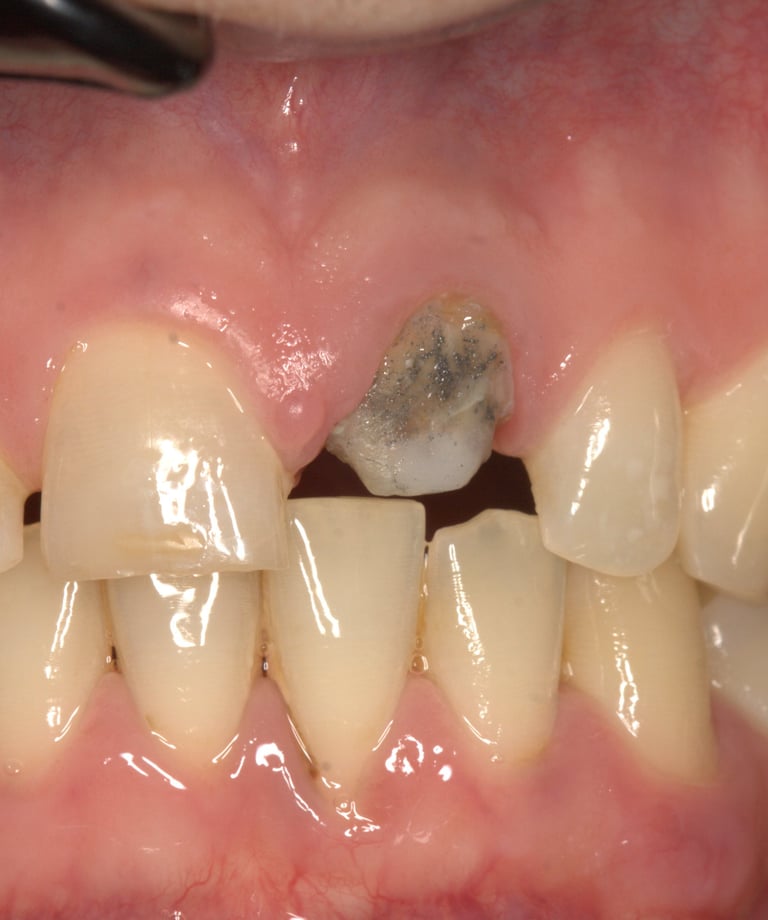

Moncone non ritentivo

Moncone ritentivo